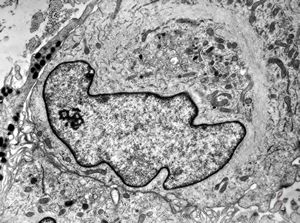

F, 57y. | mycosis fungoides … cerebriform nucleus of Sézary cell